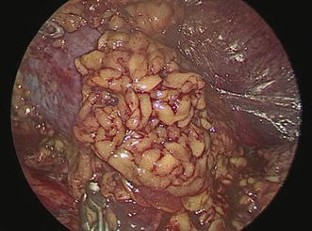

Laparoscopic partial nephrectomy without intracorporeal suturing

Partial nephrectomy has gained wider acceptance as a surgical technique in treating small renal tumors. Laparoscopic partial nephrectomy (LPN) still remains a technically demanding surgery to this day. We present our technique of laparoscopic partial nephrectomy, one that is performed without intracorporeal suturing.

We performed LPN on 31 patients with localized renal parenchymal tumor (stage T1). The procedures were done from September 2009 to March 2015 at the Kaohsiung Medical University Hospital and the Kaohsiung Municipal Ta-Tung Hospital. Our technique involves the covering of renal defect layer by layer with FloSeal, Tisseel and a fat pad after monopolar coagulation.

Fig. 2